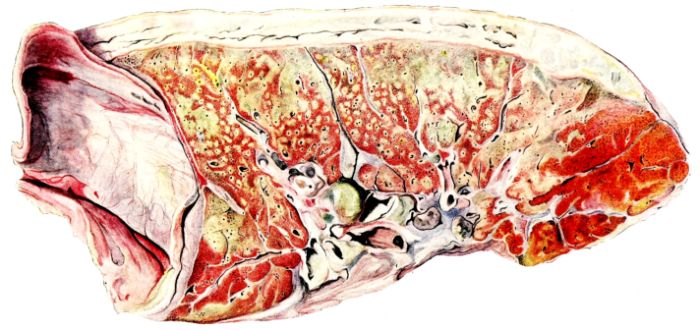

FIG. XXVII. AUTOPSY NO. 115. HERE THE HEMORRHAGIC CONSOLIDATION INVOLVES THE DEPENDENT PORTION OF THE LUNG; CONTRAST THIS WITH THE EDEMATOUS AND EMPHYSEMATOUS UPPER LOBE.

FIG. XXVIII. AUTOPSY NO. 118. THE CONSOLIDATION IS GREY IN COLOR AND LOBAR IN TYPE. IN THE CENTER OF THE HEPATIZED LOBE THERE IS A LARGE HEMORRHAGE. THE UPPER LOBE IS CONGESTED AND EDEMATOUS.

The lung remains increased in volume and its surface is mottled with vivid colors. Often these are an indication of deeper parenchymatous change. The pale pink zones, through the pleural surface of which distended alveoli are discernible, are still prominent in the upper lobe, around the margins, and on the anterior surface of the lung. The darker purple, slightly elevated, often circumscribed, infarct-like areas (25, 34, 108) may occur anywhere, but are more frequent in the lower lobes. Small, maroon, slightly depressed areas of atelectasis may also involve the borders of the lung, usually the posterior borders; or they may occur between larger and more elevated areas on either lobe. Besides the purple, firm, projecting foci, paler pink or grey nodules of similar consistence may be present and show no structure when viewed through the pleura. The distribution of the different types of change is variable, and, aside from the fact that they involve the middle and lower lobes more frequently than the upper, no general statement is possible. In a few instances, one lobe, almost always the lower, may be more voluminous than the others, and although its pleura often suggests lobular involvement, the masses tend to be confluent and suggest a pseudolobar change. Sometimes, though rarely, this approaches a true lobar type of consolidation. (Compare Figs. XIII and XXVII.) Occasionally, the changes in the lung, except its increase in size, are obscured by pleural exudate which may form a thick, buttery, rather sticky mass on the surface (12, 19, 157) (Fig. XXXVII). Such pleural exudates are rare, and likewise it is uncommon to find so little pleural granulation as in the previous group. The roughening, as a rule, is not uniform, but is more prominent over the lower lobes and in the interlobar spaces than elsewhere. It may occur when there is no definite increase in the fluid content of the pleural sac.

The lung, now sectioned, presents a surface in accord with the changes suggested from the description of its external appearance. As compared with the first stage the amount of syrupy, blood-stained exudate may be definitely decreased, especially in the upper lobe or in those portions of the lung where the solidification is less marked. Its character, too, may be more cloudy, and more ropy, or viscid; it bathes the surface and is scraped off in abundance with the blade of a knife from the underlying consolidated foci (108, 156). The bronchi and bronchioles, however, may be prominent, irrespective of the change in the parenchyma itself. From their lumina, thick, yellow pus wells forth and their mucous membrane is intensely congested. Where such involvement occurs in unconsolidated portions of the 24lung, the bronchioles are even more striking than in the hepatized areas in which the more widespread changes obscure the process. The dilatation of the bronchioles, especially in their smaller ramifications, is still conspicuous.

The consolidated areas vary greatly in size and number;[10] often they are small and involve only single lobules, which now stand out as granular, generally elevated patches on the surrounding congested plane. Their color, as on the pleura, varies. They may be dark, almost hemorrhagic, fading through the reds, pinks, and greys. They may be firm, or, at the other extreme, honeycombed by small, often narrow, cavities, from which a material similar to that described on the surface wells forth. The latter change is more frequent if the consolidated area is large. It has occurred most often in the pseudolobar and in the lobar types of the process. The pseudolobar change is differentiated, not only by the confluence of more or less definite lobular patches and by its involvement of portions of contiguous lobes rather than a single lobe, but also by variations in the color and consistence of the different lobular foci. This is in contrast with lobar involvement where the entire lobe is affected by a uniform process usually at the same stage of development. Although the consistence may vary in different portions, usually the same color is present throughout. (Compare Figs. XIV and XXVIII.) In one instance where a solid, yellow lobe was found, its center contained an irregular, fresh blood clot (Fig. XVIII), which would be sufficient to differentiate this type of consolidation from that of respiratory disease in which the initial lesion is less destructive. Sometimes the softening in a hepatized lobule or group of lobules is much more evident, and the zone becomes divided by irregular channels filled with viscid, grey or brown material (108, 149, 162). When such a condition lies just beneath the pleural surface, it may be distinctly seen from without (Fig. XXXIII). The pleura bulges, the normal topography of the local zone is lost, and it appears as a dull, somewhat projecting, circumscribed patch, two or three or more centimeters in diameter, the surface of which has a more or less characteristic brown or brownish black opacity. As soon as this is sectioned there pours from the cavity the liquefied exudate in which the destroyed pulmonary parenchyma is mixed (Fig. XXXIV). Occasionally, strands of tissue still traverse the cavity, but, as a rule, it empties itself completely, and leaves a brownish black wall. The delicate, sweet but persistent and penetrating odor is not so marked as with typical gangrene.